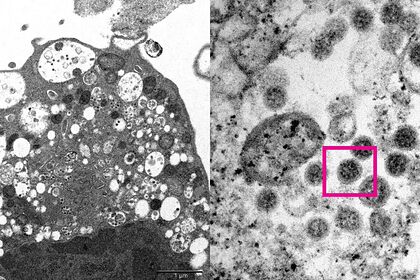

Ученым из Университета Гонконга впервые удалось сфотографировать омикрон-штамм коронавируса. Об этом сообщается на сайте научного учреждения.

Исследователи сделали электронную микрофотографию клетки (Vero E6) почки обезьяны, инфицированной омикроном. На ней они увидели повреждения с набухшими везикулами, содержащими вирусные частицы. При сильном увеличении им удалось разглядеть скопления характерных сферообразных объектов с шипами в форме короны на их поверхности.